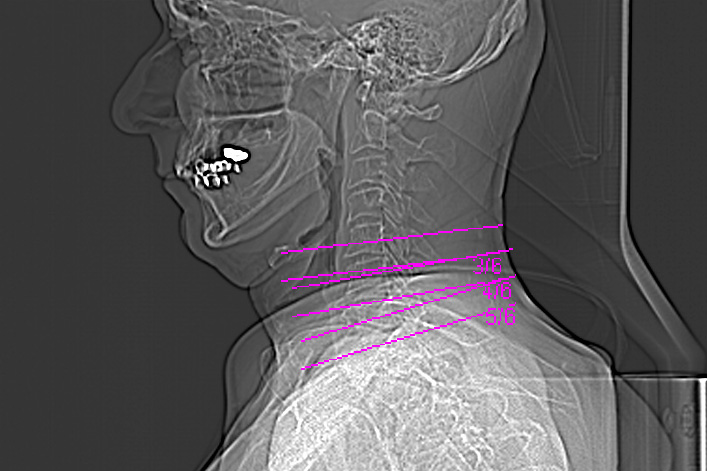

Für das Bild der Woche wurde dieses Mal eine besondere Vorrichtung benutzt. Auf Grund ständiger Schmerzen im rechten Oberarm suchte ich meinen Hausarzt auf. Nach einer kurzen Untersuchung vermutet er etwas im Halswirbelbereich und schickte mich zum Radiologen. Dort wurde eine Computer Tomografie (CT) gemacht. Die Bilder erhielt ich auf einer CD für meinen Hausarzt.

Und weil ich nun mal neugirig bin, legte ich die CD in das Laufwerk meines Rechners und siehe da, es tat sich was. Auf der CD ist ein Viewer, mit dem man sich die Ergebnisse der CT ansehen kann. Sieht schon toll aus, nur deuten kann ich es nicht. Fahren Sie mal mit der Maus in das Bild. Dann bekommen Sie einen kleinen Eindruck von den verschiedenen Schichten. Mal sehen, was mein Hausarzt in der nächsten Woche dazu sagt....